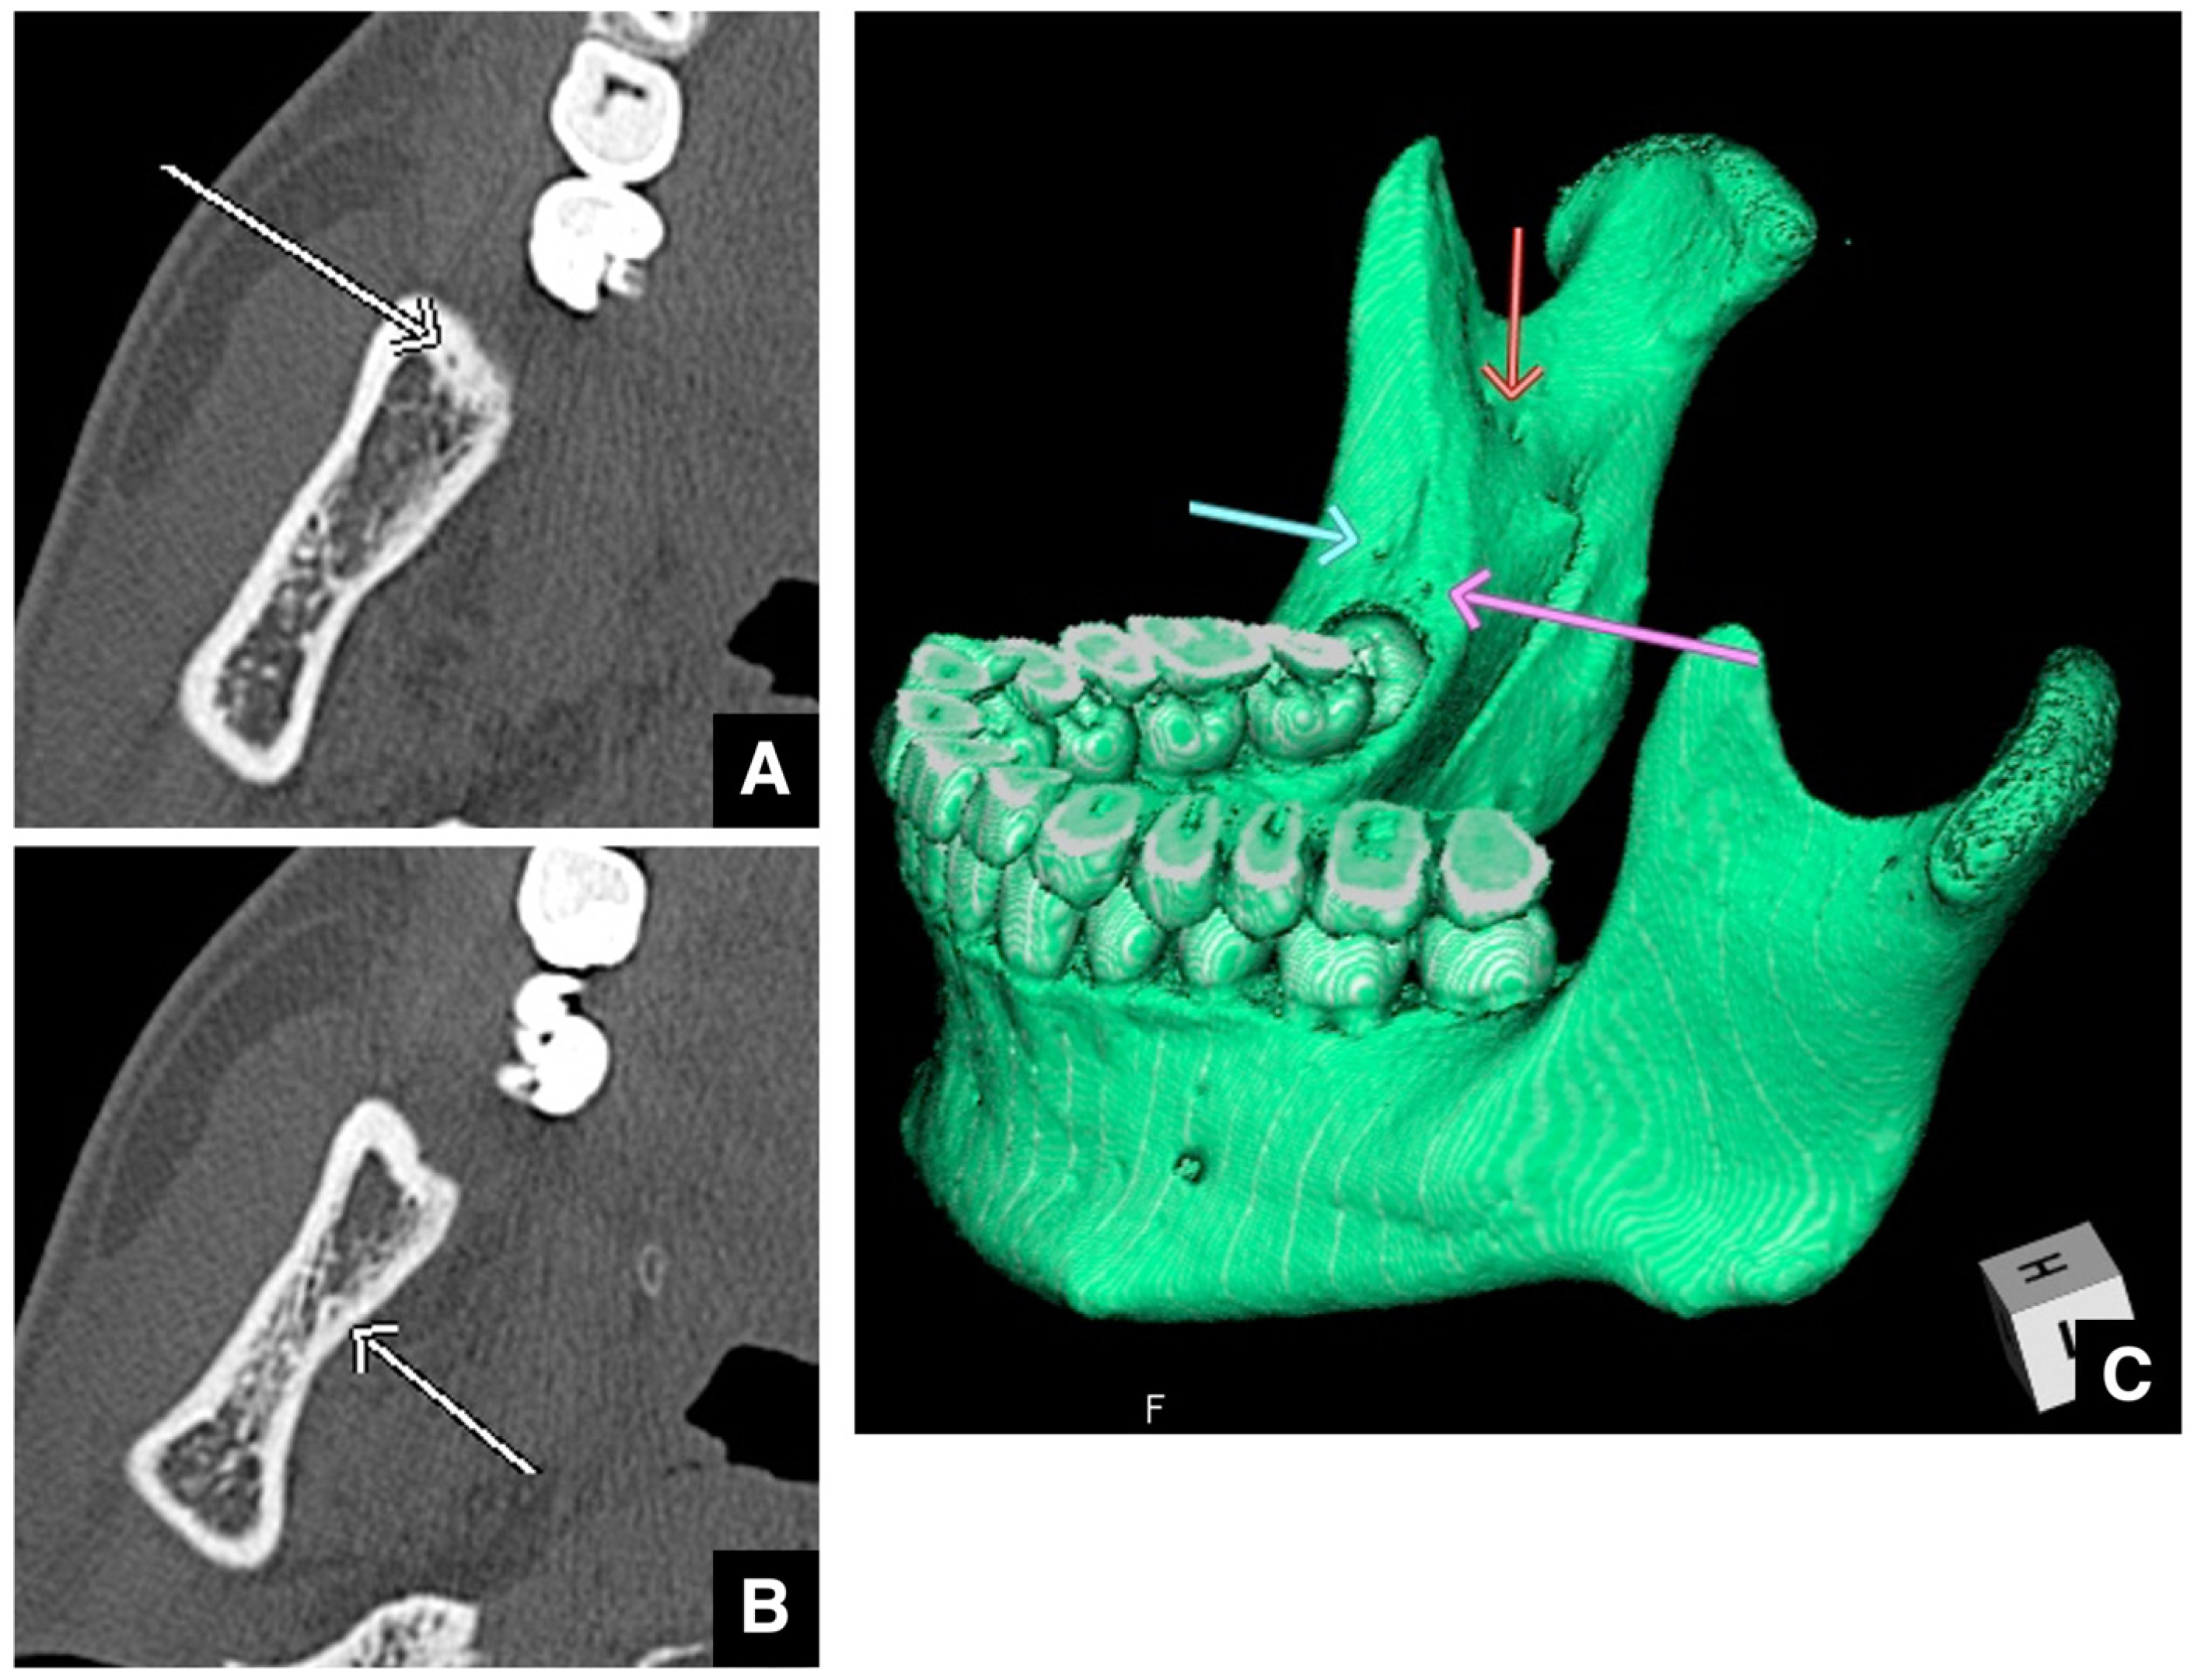

| Setting the osteotomy line 1. Evaluation of the position of the mandibular canal and surrounding bone quality Presence or absence of mandibular canal bifurcation and course of resection site Distance from the buccal wall of the mandibular canal to the buccal cortical bone margin Bone quality around the mandibular canal (CT number) 2. Distance from the mandibular notch to the lingula Whether it is 14 mm or more 3. Morphology of the mandible and variation in cortical bone thickness Cortical bone thickness in the medial osteotomy area and lateral osteotomy area Enhanced safety through improved visibility 1. Medial curvature of the mandibular ramus Mandibular ramus is straight or strong curvature 2. Course of small blood vessels along the bone surface Depression of the buccal-lingual cortical bone from the mandibular fossa to the mandibular ramus region, trabecular bone defect Improved success rates through enhanced postoperative bone integration 1. Degree of interference between bone segments The presence or absence of interference between the proximal and distal bone segments formed during virtual mandibular deformity surgery |

- Yoshioka, I.; Tanaka, T.; Oda, M.; Kodama, M.; Habu, M.; Kito, S.; Okabe, S.; Wakasugi-Sato, N.; Kuroiwa, H.; Tominaga, K.; et al. Usefulness of CT scan images for planning the bone cut for intra-oral vertical ramus osteotomy. J. Oral Maxillofac. Surg. 2008, 7, 245–250. [Google Scholar]

- Yoshioka, I.; Tanaka, T.; Khanal, A.; Habu, M.; Kito, S.; Kodama, M.; Oda, M.; Wakasugi-Sato, N.; Matsumoto-Takeda, S.; Fukai, Y.; et al. Relationship between inferior alveolar nerve canal positions at the mandibular second molar in patients with prognathism and the possible occurrence of neurosensory disturbance after sagittal split ramus osteotomy. J. Oral Maxillofac. Surg. 2010, 68, 3022–3027. [Google Scholar] [CrossRef]

- Yoshioka, I.; Tanaka, T.; Habu, M.; Oda, M.; Kodama, M.; Kito, S.; Seta, Y.; Tominaga, K.; Sakoda, S.; Morimoto, Y. Effect of bone quality and position of the inferior alveolar nerve canal in continuous, long-term, neurosensory disturbance after sagittal split ramus osteotomy. J. Craniomaxillofac. Surg. 2012, 40, 178–183. [Google Scholar] [CrossRef] [PubMed]

- Shah, N.P.; Murtadha, L.; Brown, J. Bifurcation of the inferior dental nerve canal: An anatomical study. Br. J. Oral Maxillofac. Surg. 2018, 56, 267–271. [Google Scholar] [CrossRef] [PubMed]

- von Arx, T.; Bornstein, M.M. The bifid mandibular canal in three-dimensional radiography: Morphologic and quantitative characteristics. Swiss Dent. J. 2021, 131, 10–28. [Google Scholar] [CrossRef]

- Aung, N.M.; Myint, K.K. Bifid mandibular canal: A proportional meta-analysis of computed tomography studies. Int. J. Dent. 2023, 2023, 9939076. [Google Scholar] [CrossRef]

- Yoshioka, I.; Tanaka, T.; Khanal, A.; Habu, M.; Kito, S.; Kodama, M.; Oda, M.; Wakasugi-Sato, N.; Matsumoto-Takeda, S.; Seta, Y.; et al. Correlation of mandibular bone quality with neurosensory disturbance after sagittal split ramus osteotomy. Br. J. Oral Maxillofac. Surg. 2011, 49, 552–556. [Google Scholar] [CrossRef] [PubMed]